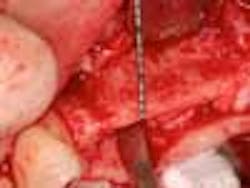

Fig. 2